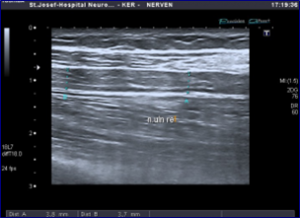

Υπέρηχος του ωλενίου νεύρου του άνω άκρου με εμφάνιση παθολογικού οιδήματος

Ο υπέρηχος των περιφερικών νεύρων και των μυών αποτελεί μία εξειδικευμένη εξέταση, που πραγματοποείται με τη χρήση ειδικών πομπών υπερηχητικών κυμάτων (συχνότητας > 12 Mhz) και καθιστά δυνατή τη λεπτομερή απεικόνιση της δομής των αντίστοιχων νεύρων ή μυών.